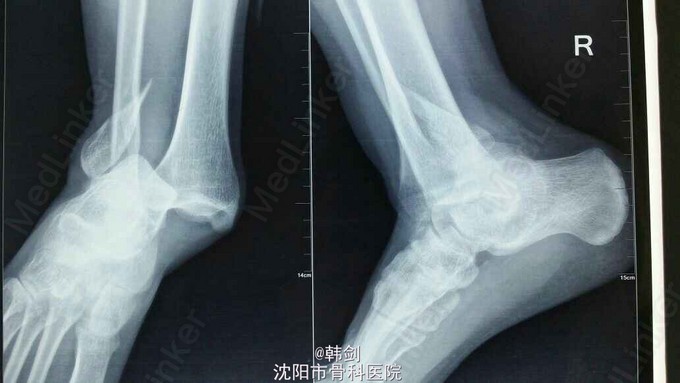

主诉:右踝外伤后肿痛,畸形,活动受限1小时。 现病史:患者于2015年9月2号晚摔伤右踝,当即肿痛,畸形,活动受限,急来诊我院,经急诊拍片,阅片及查体后以“右踝骨折”收入院。

诊断:右外踝骨折伴胫距关节脱位及内侧韧带损伤。 治疗:患者入院后,完善各项检查,行手法复位,效果不佳,于9月13日行手术治疗。三维CT为复位后拍摄。